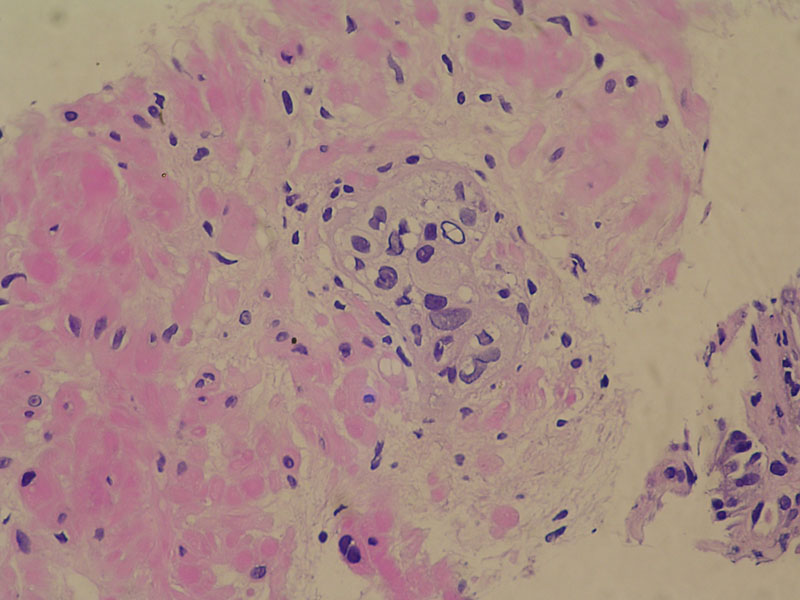

Caso Nº 1:

Paciente de 80 años, con carcinoma prostático diagnosticado hace 4 años, tratado con radioterapia.

Diagnóstico:

Cilindros biópsicos de Próstata con lesiones por radioterapia.